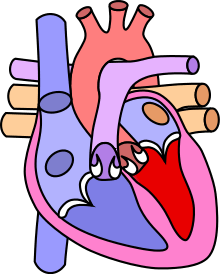

| Diagram of a healthy heart and one with tetralogy of Fallot | |

As such, by definition, tetralogy of Fallot involves four heart malformations which present together:

There is anatomic variation between the hearts of individuals with tetralogy of Fallot. Primarily, the degree of right ventricular outflow tract obstruction varies between patients and generally determines clinical symptoms and disease progression.